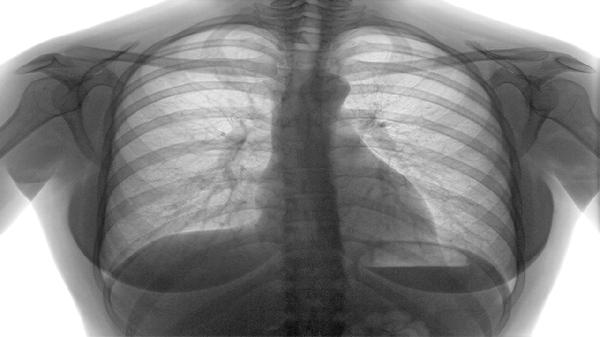

两类疾病在急性发作诱因上存在交叉,但慢阻肺急性加重多由感染触发,哮喘发作常因接触过敏原或冷空气诱发。诊断需结合病史、肺功能检查及影像学结果,部分患者可能同时存在哮喘-慢阻肺重叠综合征。无论确诊何种疾病,均需避免吸烟及有害环境暴露,定期监测肺功能,接种流感疫苗和肺炎疫苗有助于降低急性发作风险。